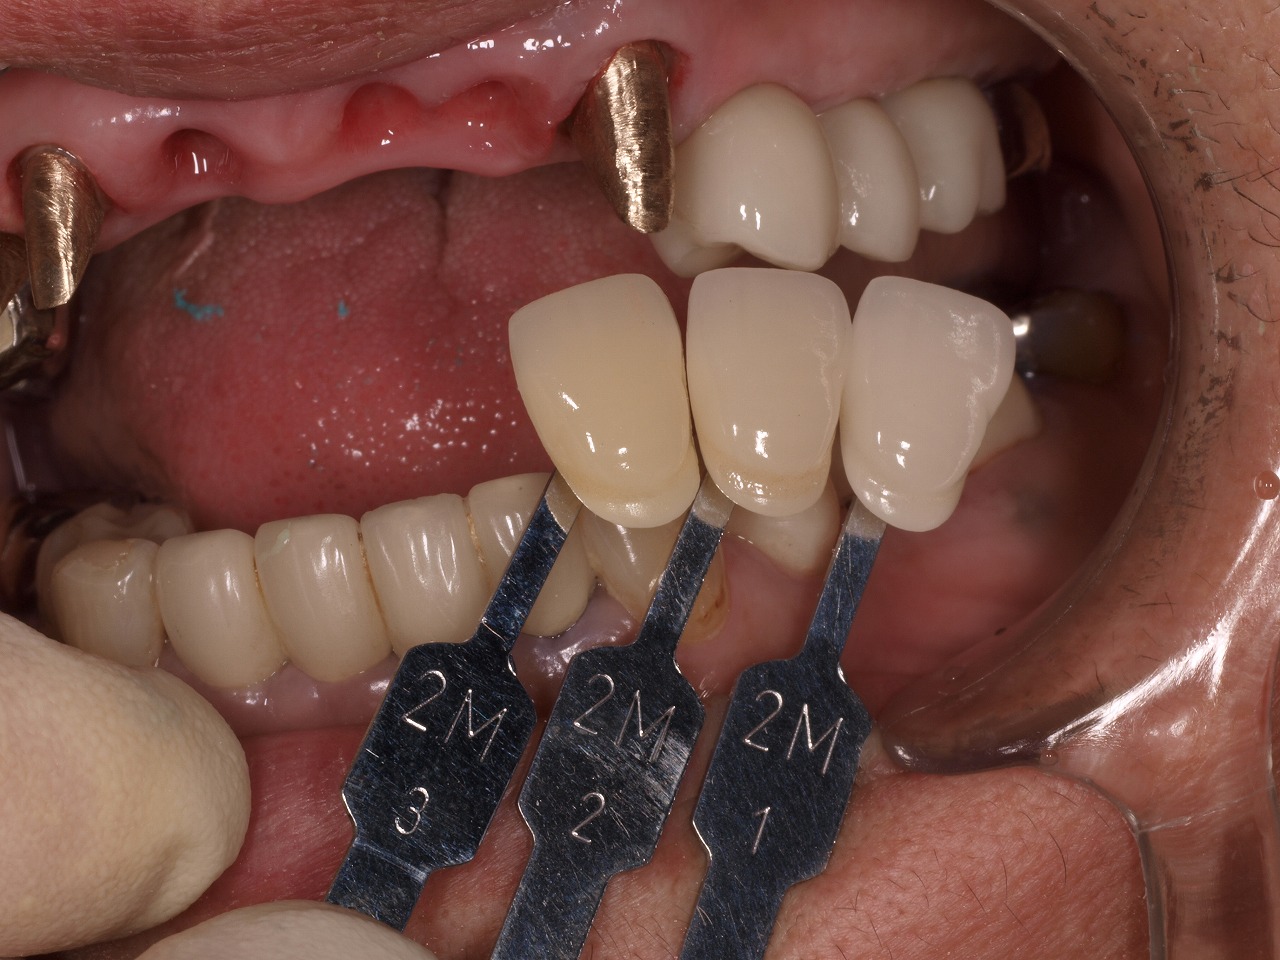

全顎にインプラントも含めた支持の仮歯が入りました

これより仮歯を入れていきます

このようにプロビジョナルが入りました

プロビジョナルにて前歯部は歯肉の形態を作成しています

スキャロップ状態のきれいな歯茎が立ち上がりました

この操作をしないと前歯部のインプラントでは審美的にきれいに仕上がりません